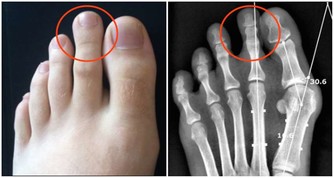

1、增加維生素D的代謝:Phenytoin(癲癇治療)、Phenobarbital(癲癇治療)。

2、增加骨代謝:Valproicacid(精神科用藥)、Cyclosporin(控制器官移植後排斥作用)、Heparin(血栓性栓塞症及其預防)。

3、減少骨生成:Ifosfamide(抗癌藥)、Prednisolone(緩解發炎及過敏癥狀)。

4、減少血清鈣的濃度:Carbamazepine(癲癇治療、三叉神經痛)。